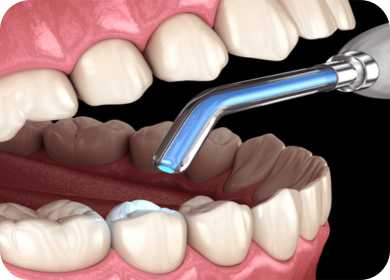

At Shraddha’s Complete Dental Care & Implant Center, our general dentistry services are the foundation of a healthy smile. We focus on prevention, early detection, and effective treatment of common dental issues to ensure your teeth and gums remain in excellent condition. From regular dental check-ups and professional cleanings to restorative procedures, we provide comprehensive care for patients of all ages. Using the latest technology and gentle techniques, we make every visit comfortable while helping you maintain strong, healthy, and beautiful teeth for life.

We specialize in tooth-colored, minimally invasive fillings that restore decayed or damaged teeth while preserving as much natural tooth structure as possible. Using advanced composite materials, we match the filling to your tooth’s natural shade for a strong, durable, and aesthetically pleasing result.